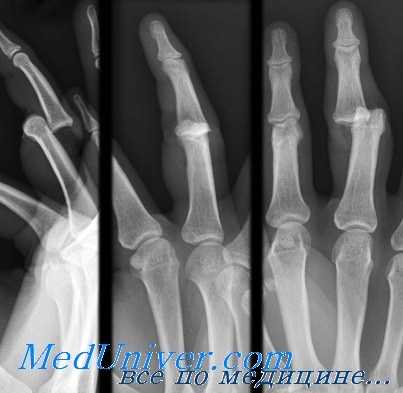

Вывихи в межфалантовых суставах. Диагностика, лечение

Вывих в проксимальном межфаланговом суставе (ПМФС) может произойти в любом из трех направлений — тыльном, ладонном или боковом. Тип вывиха определяется положением средней фаланги относительно проксимальной. Чаще всего, обычно во время спортивных игр с мячом, происходит тыльный вывих. Механизм травмы связан с переразгибанием в ПМФС.

Смещение к тылу может явиться следствием повреждения только капсульно-связочного комплекса или может быть составным элементом переломовывиха. Значительное осевое воздействие увеличивает вероятность отрыва суставного края средней фаланги с ладонной стороны. Вправление вывиха достигают тракцией по оси за среднюю фалангу. Манипуляцию осуществляют под проводниковой анестезией. По окончании вправления следует выполнить рентгенологическое исследование, чтобы убедиться в точности репозиции, и провести пробу на боковое отклонение дистальных отделов для исключения повреждений коллатеральных связок.

Пробы проводят как при полном разгибании в суставе, так и при 30° сгибании. Если сустав стабилен, то ранние движения должны страховаться шинированием. При выявлении нестабильности уточняют степень боковой девиации, после чего палец сгибают еще на 10° в ПМФС и накладывают фиксирующую шину по тыльной поверхности, которая препятствует разгибательным движениям. Еженедельно увеличивают угол разгибания на 10° до достижения полного разгибания средней фаланги.

Ладонные вывихи в проксимальном межфаланговом суставе встречаются гораздо реже, чем тыльные, и могут быть двух разновидностей. При первом типе повреждающие силы воздействуют на выпрямленный палец и вызывают смещение основания средней фаланги в ладонную сторону с отрывом центральной ножки сухожильного растяжения. В таких случаях возможно закрытое вправление путем вытягивания по оси средней фаланги. Фиксирующую шину накладывают на шесть недель в положении разгибания в ПМФС, при этом дистальный межфаланговый ДМФС оставляют свободным для сгибания и разгибания.

Ко второму типу повреждений относится ротационный подвывих, который происходит под воздействием силы, приложенной к полусогнутому пальцу. Результатом становится расслоение центральной и боковой ножки сухожильного растяжения, а в образовавшуюся щель попадает выступ основания средней фаланги. Закрытое вправление может оказаться затруднительным, но можно попытаться согнуть пальцы в ПФС и ПМФС и осторожно сместить среднюю фалангу в правильное положение. При неудаче лучше перейти к вправлению открытым способом, чем повторять попытки закрытого вправления.

Дальнейшая тактика, если не повреждена центральная ножка сухожильного растяжения, состоит в раннем восстановлении движений в фиксированном к соседнему пальцу положении. При разрыве центральной ножки лечение проводят как при любых повреждениях центрального сухожильного растяжения, а именно, накладывают на шесть недель фиксирующую шину при разогнутом ПМФС.

Вывихи в боковую сторону являются результатом разрыва ладонной пластинки и одной из коллатеральных связок. В клинической картине преобладают отечность и болезненность на стороне поврежденной связки. Как правило, вывих относительно легко устраняется путем тракции и вправления средней фаланги. Фиксацию разогнутого пальца осуществляют гипсовой лонгетой в течение двух недель с последующими содружественными движениями с соседним пальцем.

Вывихи в дистальном межфаланговом суставе чаще всего бывают тыльные и боковые, и во многих случаях являются открытыми повреждениями из-за тонкого слоя окружающих мягких тканей. Лечение закрытых повреждений выполняют тракцией по оси дистальной фаланги. Открытые вывихи вправляют на фоне начатой антибактериальной терапии и после надлежащей санации сустава. В отдельных случаях причиной невправимых вывихов становится интерпозиция проксимальной ладонной пластинки или сухожилия сгибателя. Иммобилизацию в течение одной недели осуществляют в положении легкого сгибания, после чего проводят содружественную фиксацию в прерывистом режиме еще на 1-2 недели.